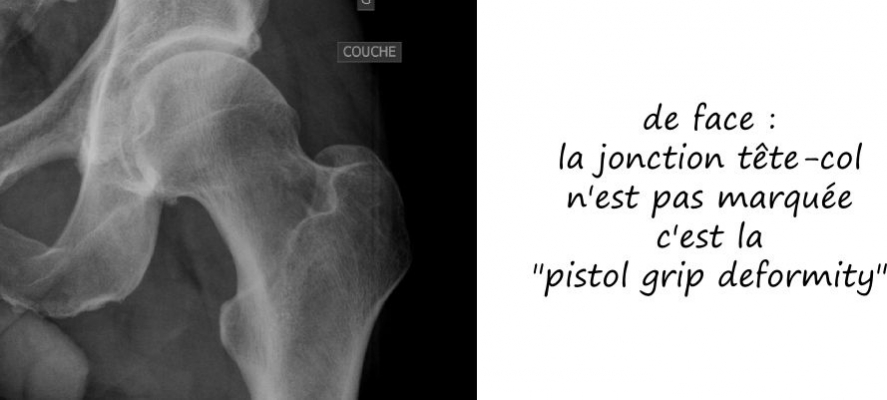

Radiologie standard

Le conflit fémoro acétabulaire se décèle sur de simples radiographies de la hanche, notemment sur le profil de DUNN qui expose la face antérieure du col fémoral. Sur cette radio est estimée l’angle alpha, correpondant à l’angle formé par l’axe du col fémoral et une droite passsant par le centre de la tete fémorale et le point de décrochage de la jonction tete-col, et qui est normalement de l’ordre de 45°; il est augmenté dans les conflits par effet came, comme sur cette radio ci dessous.